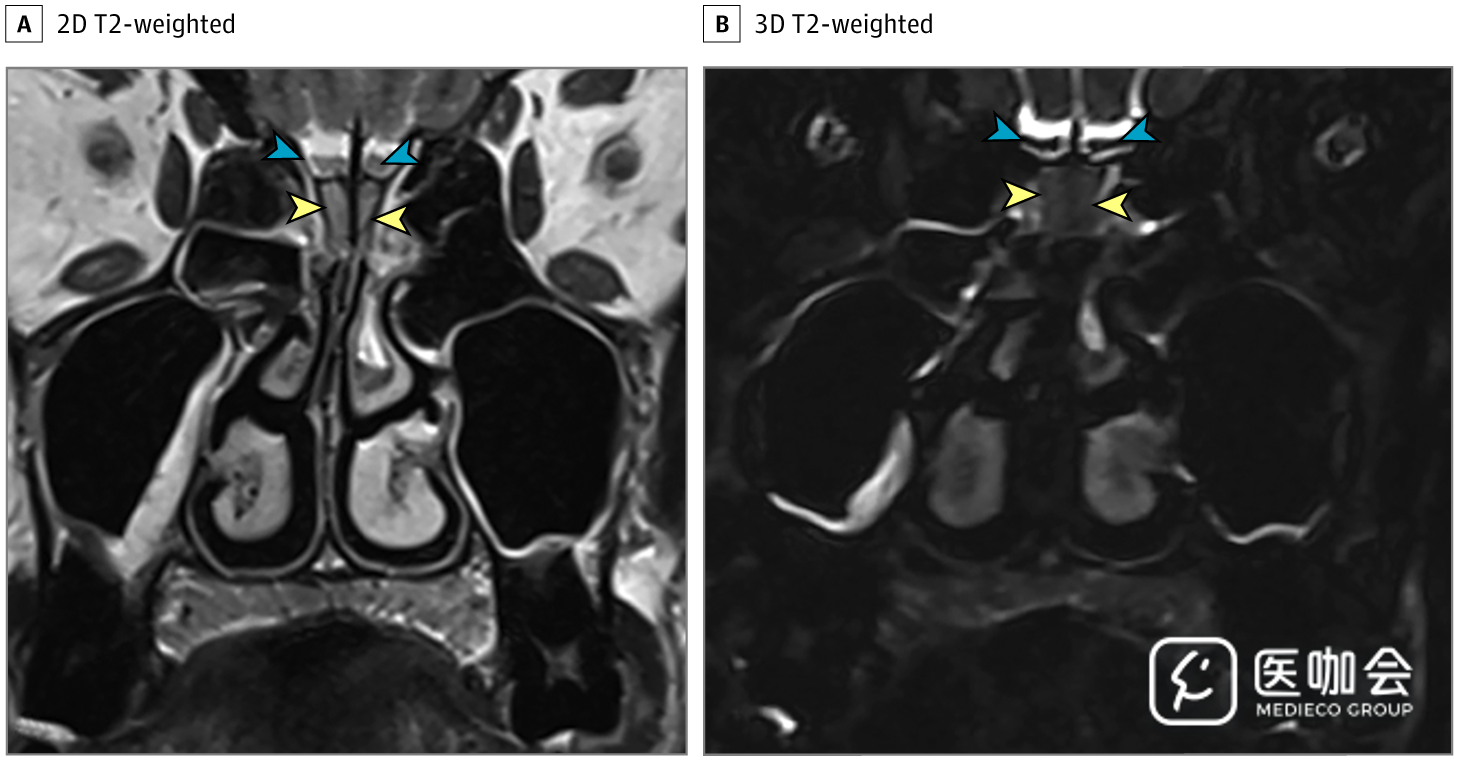

患者接受了鼻腔CT检查(图1),显示双侧嗅裂区的炎性阻塞,经鼻腔MRI再次确认了这一结果(图2)。患者的嗅球和嗅神经束未见异常。由于她的丈夫被怀疑感染了SARS-CoV-2,因此该患者也接受了SARS-CoV-2的RT-PCR,结果呈阳性。

图2